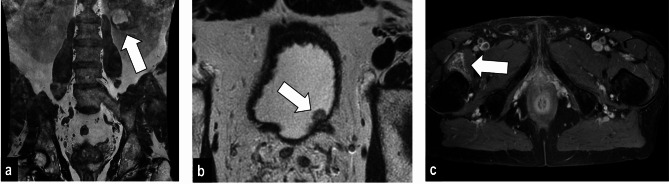

Background: Despite the increasing interest in abbreviated protocols, we adopted an extended protocol for all prostate MRIs. In this study, we assessed the benefits of an extended prostate MRI protocol, measured by the number and the clinical importance of additional findings (AFs) and their impact on patient management.

Methods: In a single-center study, we retrospectively included 1282 patients undergoing prostate MRI between 01.10.2018 and 30.04.2022. Additional findings were defined as any pathology not located in the prostate or the seminal vesicles. These were classified as related or unrelated to prostate cancer (PCa). The latter were divided into groups based on low, moderate, or high clinical significance (group 1, 2, and 3). A finding unrelated to PCa was judged to be clinically significant (group 2: moderate, group 3: high) if further diagnostic investigations, or treatment was necessary. The degree of urgency of the latter determined moderate and high significance. For group 3 findings, a change in management was defined as further workup.

Results: A total of 5206 AFs was recorded in 1240/1282 patients. One hundred and twenty-three (2.4% of all findings) extra-prostatic PCa related AFs were found in 106 (8.3% of all patients) patients. The remaining 5083 (97.6% of all findings) findings were not related to PCa, of which 3155 (60.6%), 1770 (34.0%), and 158 (3.0%) were assigned to groups 1, 2, and 3, respectively. A management shift was identified in 49 (3.8% of all patients) patients of group 3.

Conclusion: The extended prostate MRI protocol shows a considerable prevalence of AFs of which more than a third are clinically significant, related or unrelated to PCa (groups 2 and 3). A substantial percentage (8.3%) of patients have extra-prostatic PCa-related AFs that change the patient's disease stage and management. However, a change in management due to AFs unrelated to PCA that belong to group 3 is observed in less than 4% of all patients. The choice between extended and abbreviated prostate MRI protocols should be made based on available resources.